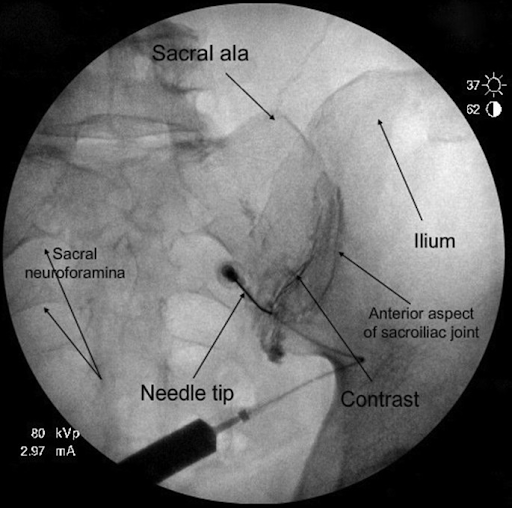

From specialistpainclinic.co.za

SI Joint Injections Specialist Pain Clinic Si Joint Forum Yes, it feels like i have been kicked. Physio myofascial release helped me return to work but pain started again. I go to the pool 4 times a week, i wear a floater round my. In that time chiropractic adjustments would help but they weren't a long term fix. I have chronic sacrialic joint dysfunction and i can tell you. Si Joint Forum.